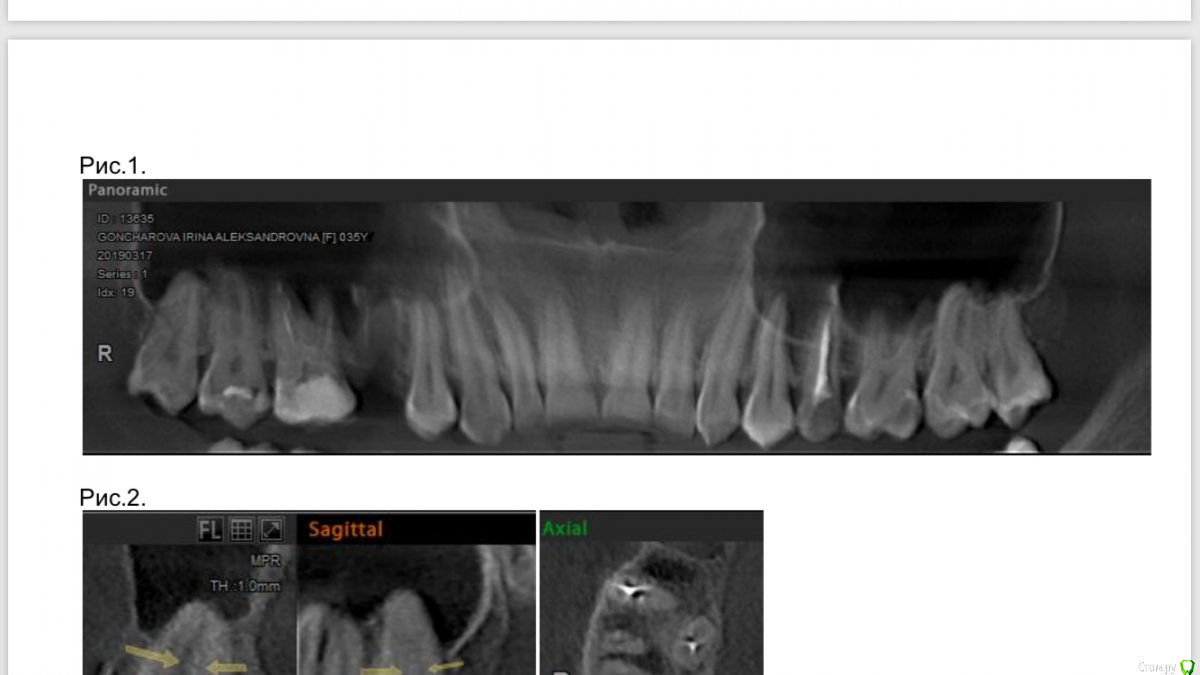

Пушканчик Опубликовано 1 апреля, 2019 Поделиться Опубликовано 1 апреля, 2019 (изменено) Добрый день, уважаемые доктора! Очень прошу помощи, т.к. уже не знаю, что мне делать. 26.12.2018 был удален 5-й верхний зуб справа, потом начался альвеолит, 14.01.2019 лунку чистили и проткнули пазуху. Был курс антибиотиков, но сама лунка заживала плохо. Примерно 28.01.2019 я стала замечать, что соседний 6-й зуб как бы выпирает, сказала об этом врачу, врач сказал, что это заживает лунка, и это нормально. Так я и ходила примерно до конца февраля. Потом начались сильные боли по всей челюсти, отдавало в ухо, под глаз и в область носа. Под глазом появился отек. Сделали ортопанораму уже в другой клинике, это было 02.03.2019 - небольшое затемнение в корнях верхнего правого 6-ого. 09.03.2019 вскрыли этот зуб и стали чистить каналы, до этого они были запломбированы гуттаперчей в 2016 г. Положили кальций, небольшое улучшение, потом опять все заболело, 19.03.2019 - снова кальций, нашли 4-й канал, результата нет, 29.03.2019 - другой врач чистила каналы, сказала, что были плохо пройдены, опять кальций - стало полегче, но щека так и болит, отек не сходит, зубы по верхней челюсти справа немеют, также отдает боль в нижние 6 и 7, тоже справа. Есть ли смысл дальше продолжать лечение? или лучше уже удалить его? Очень боюсь удаления, т.к. корни этого зуба выходят в пазуху. Есть КТ от 17.03.2019. Помогите, пожалуйста! Изменено 1 апреля, 2019 пользователем Пушканчик Ссылка на комментарий